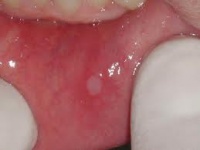

Aftas bucales. Úlceras que aparecen sobre cualquier superficie mucosa de la boca. Sus localizaciones más frecuentes son, en orden decreciente, las mucosas oral y labial, los bordes de la lengua, los surcos bucales y linguales y el paladar blando, pero no sobre la encía.

Son llagas poco profundas y dolorosas que aparecen dentro de su boca. Usualmente son de color rojo o algunas veces pueden tener una capa de color blanco recubriéndolas. Le pueden dar en la parte interna de los labios, en la parte interna de sus mejillas, en la base de sus encías o debajo de la lengua. Las aftas dolorosas son distintas de los fuegos (herpes labial) que usualmente están en la parte externa de sus labios o en los extremos de su boca.

La lesión comienza con una sensación quemante; después aparece una mácula rojiza, pequeña, seguida de una vesícula, la cual se rompe y se forma la úlcera que consiste en un punto amarillo claro, generalmente ovalado, de un milímetro a un centímetro de diámetro. Puede presentarse con una o más lesiones recubiertas de una capa amarillenta sobre una base roja, las cuales tienden a recurrir. Por lo general comienzan con una sensación de ardor en el sitio de la futura úlcera. Al cabo de varios días progresan a una tumefacción que se vuelve ulcerosa. El área de color gris, blanca o amarillenta se debe a la formación de fibrina, una proteína asociada con la coagulación de la sangre.